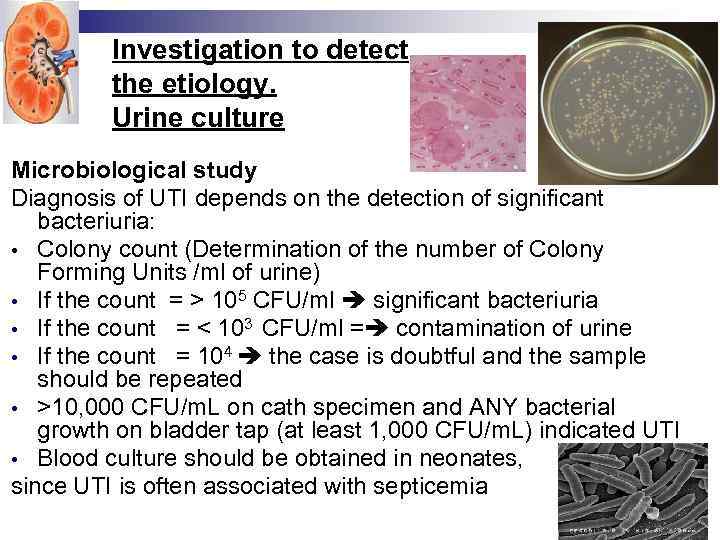

Investigation to detect the etiology. Urine culture Microbiological study Diagnosis of UTI depends on the detection of significant bacteriuria: • Colony count (Determination of the number of Colony Forming Units /ml of urine) • If the count = > 105 CFU/ml significant bacteriuria • If the count = < 103 CFU/ml = contamination of urine • If the count = 104 the case is doubtful and the sample should be repeated • >10, 000 CFU/m. L on cath specimen and ANY bacterial growth on bladder tap (at least 1, 000 CFU/m. L) indicated UTI • Blood culture should be obtained in neonates, since UTI is often associated with septicemia

Investigation to detect the etiology. Urine culture Microbiological study Diagnosis of UTI depends on the detection of significant bacteriuria: • Colony count (Determination of the number of Colony Forming Units /ml of urine) • If the count = > 105 CFU/ml significant bacteriuria • If the count = < 103 CFU/ml = contamination of urine • If the count = 104 the case is doubtful and the sample should be repeated • >10, 000 CFU/m. L on cath specimen and ANY bacterial growth on bladder tap (at least 1, 000 CFU/m. L) indicated UTI • Blood culture should be obtained in neonates, since UTI is often associated with septicemia